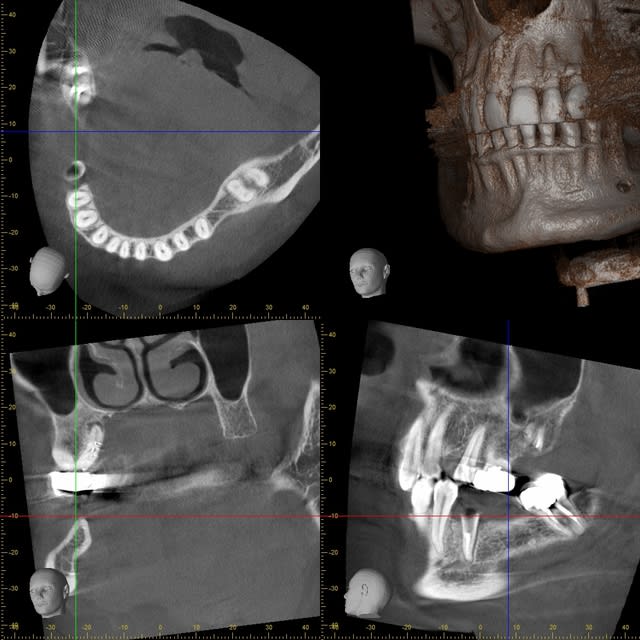

comme je suis de garde ce matin, j'ai donc le temps de poster un petit cas récemment terminé avec les nouveaux greffon d'os cortical biobank.

photos

6 3d avant

je ne sais pas pourquoi mais toutes les photos ne sont passées

le scan à 4 mois

pour l'implant 44 j'avais mis de l'os autogène et une membrane osseogard